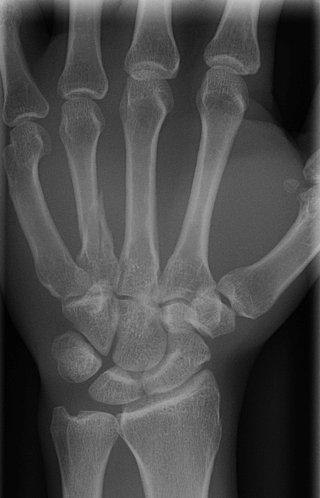

Return to Metacarpal Fracture